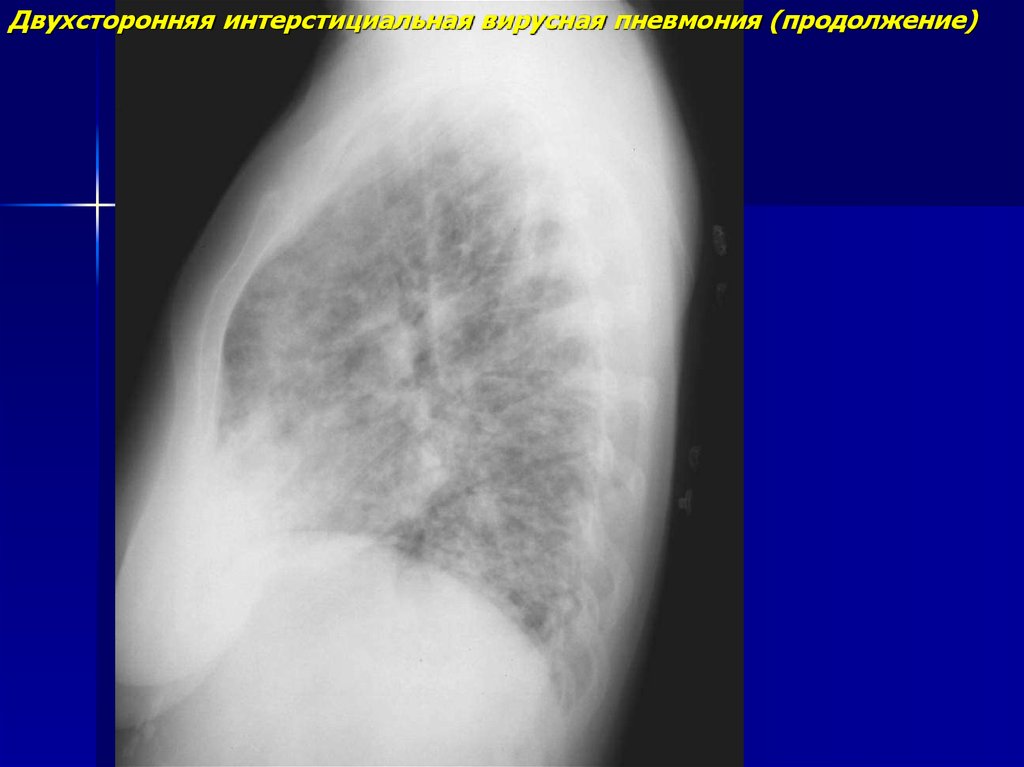

Двухсторонняя интерстициальная вирусная пневмония (продолжение)

7.